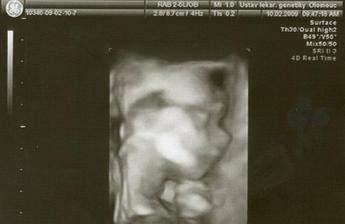

10.2.poslední genetický UTZ v Olomouci, kde nám potvrdili, že miminko je zdravé..Podle pana primáře čekáme tentokrát holčičku..